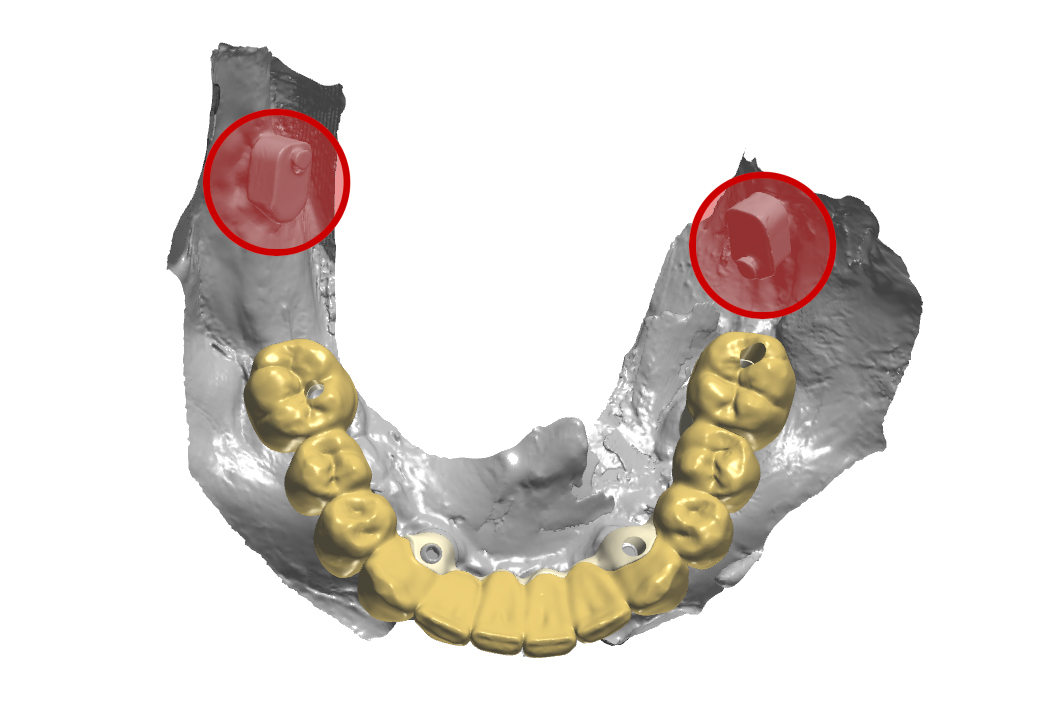

Prospettiva dall’alto della protesi inferiore

Fig. 9. (b) Prospettiva dall’alto della protesi inferiore, in evidenza gli Scan Ske.

Prospettiva laterale sinistra della protesi in occlusione

Fig. 9. (c) Prospettiva laterale sinistra della protesi in occlusione, in evidenza gli ScanSke.